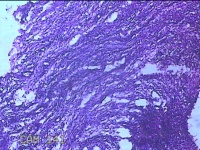

左侧卵巢囊肿⑴

性别

女

年龄

34岁

临床诊断

左侧卵巢子宫内膜异位囊肿

一般病史

下腹痛3小时入院。

标本名称

大体所见

灰白暗红色囊性肿物8x2.5x0.7cm一个,表面糜烂,部分已切开,囊内容物已流失,囊壁厚0.1cm。

图1